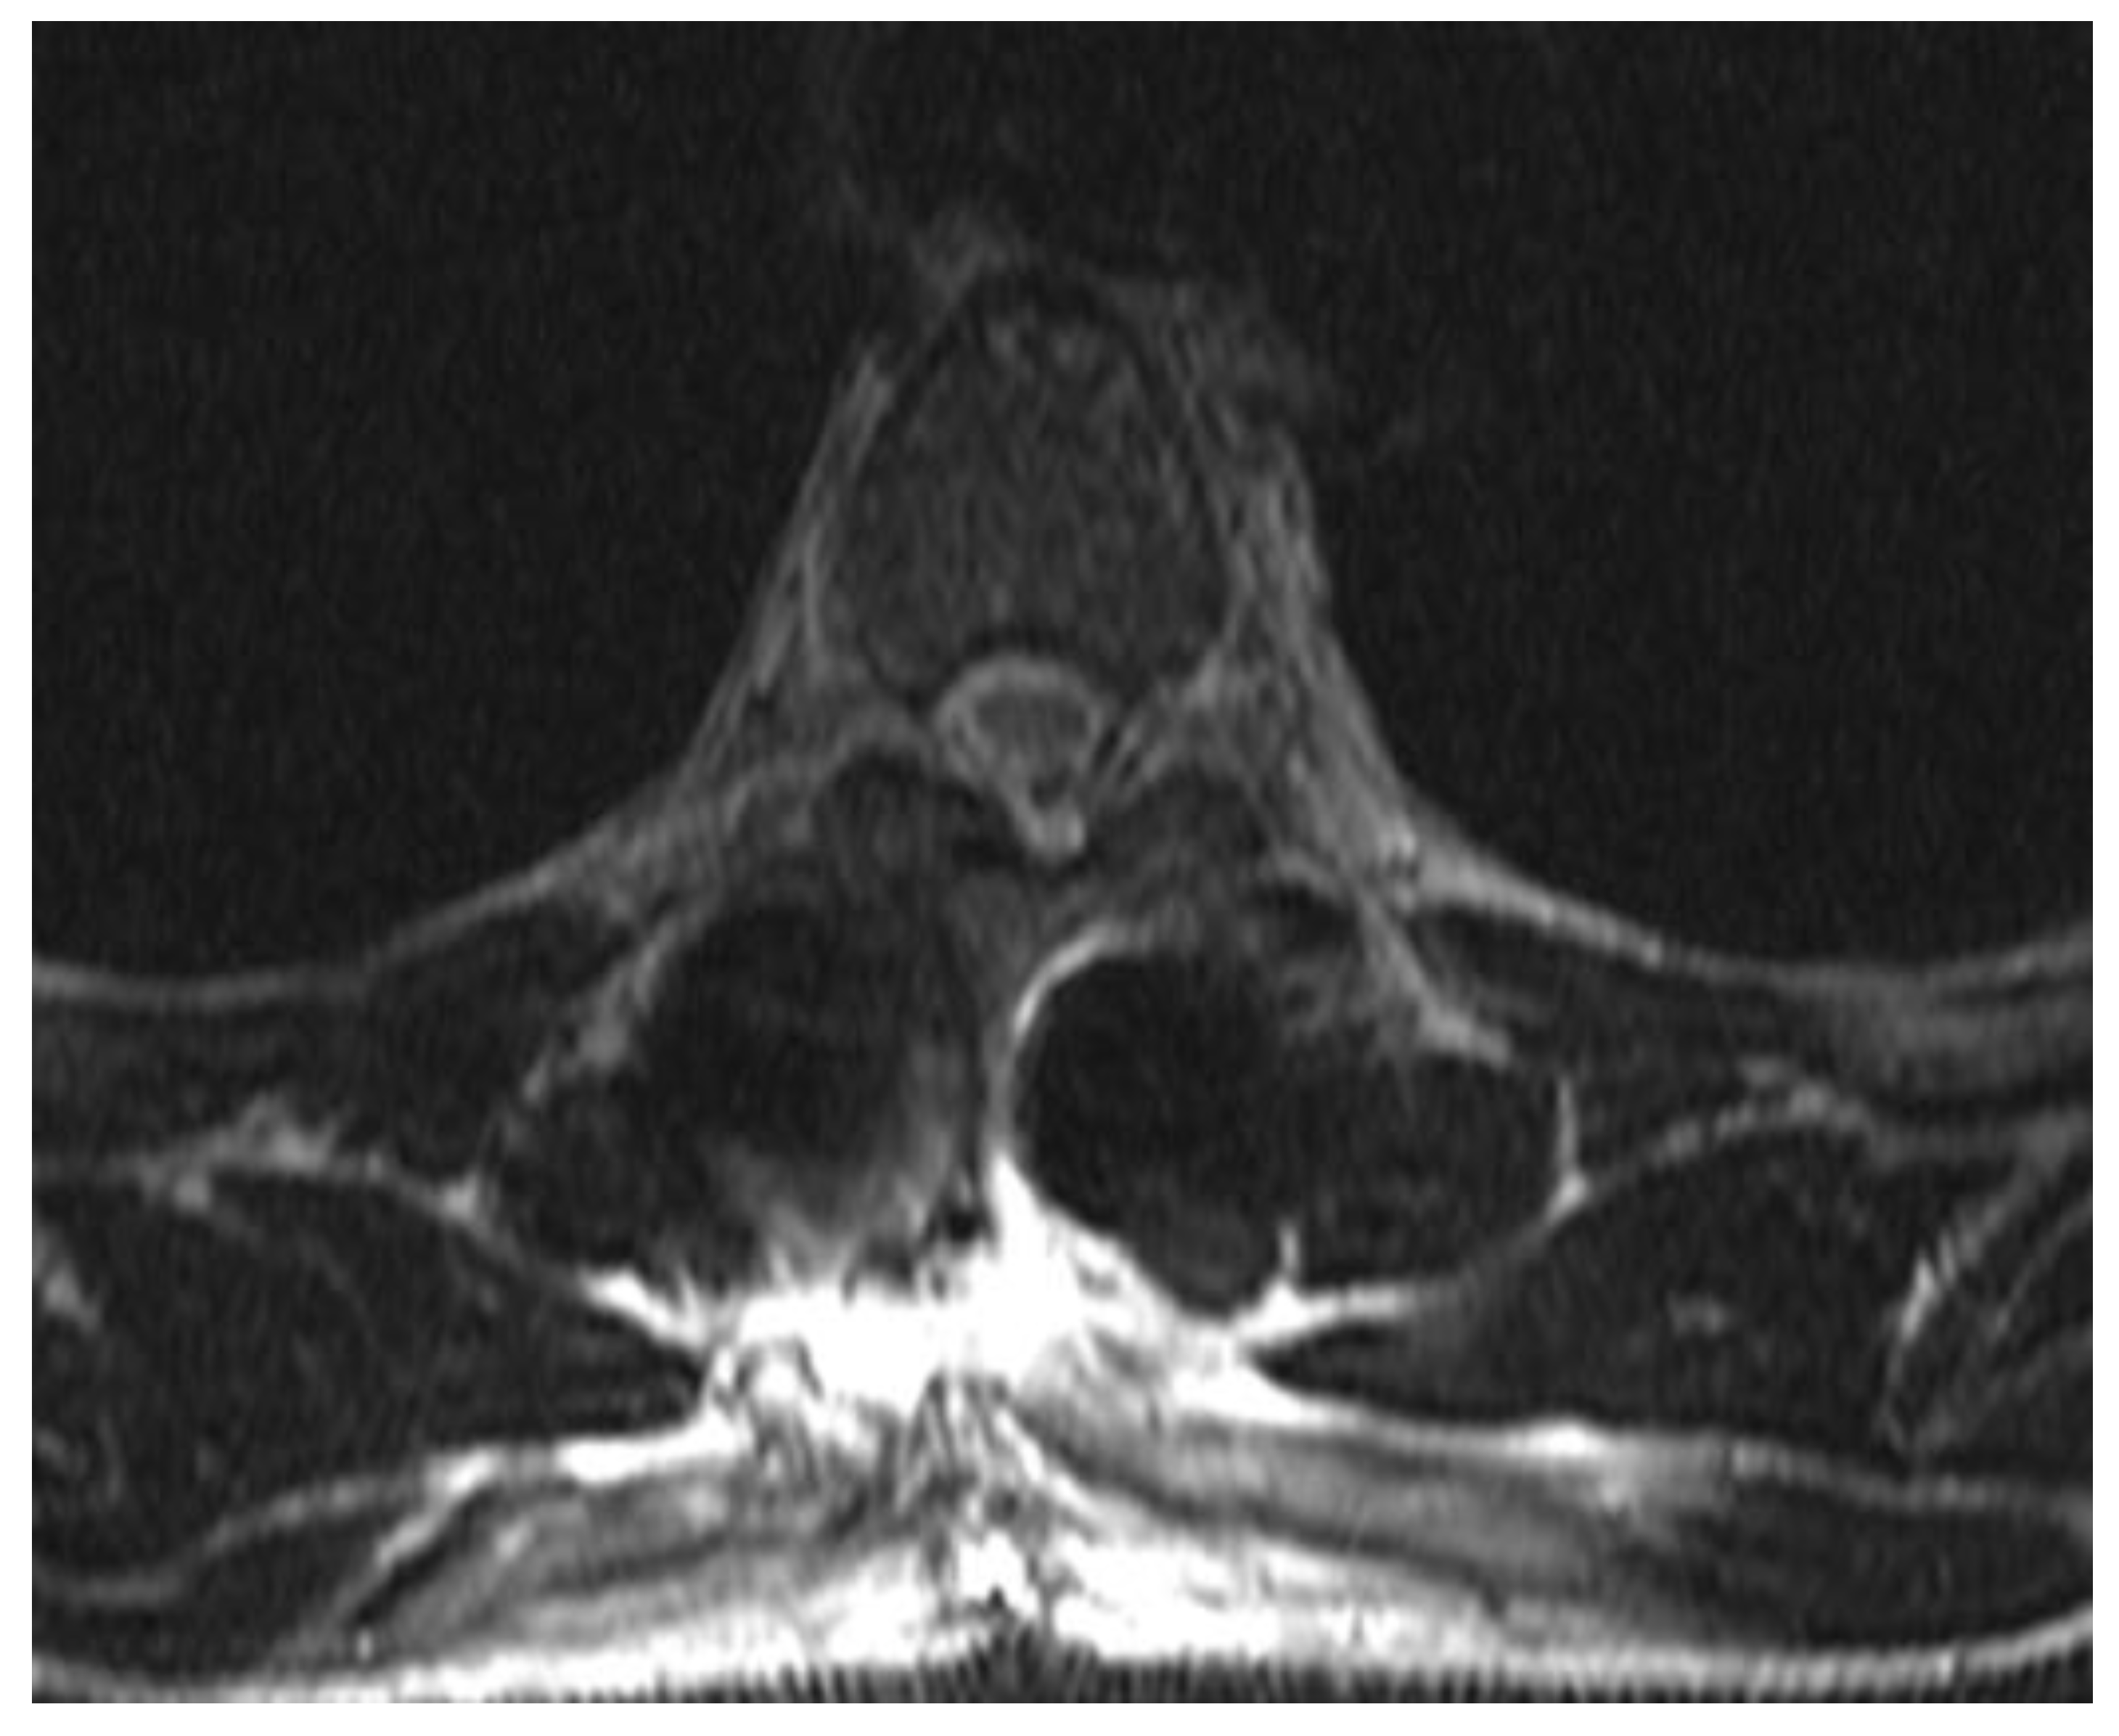

There were no fracture lines through the posterior elements or indirect signs of rupture of the tension band. Low-molecular-weight heparin was routinely applied in the evening before surgery. Spinal stabilization surgery was performed the day after admission after a brief period of preoperative preparation. Intraoperatively, no disturbance of the posterior tension band was observed (interspinous ligaments were intact, and the laminar bone showed no subtle fractures). All transpedicular screws were placed under fluoroscopic guidance in 2 planes as shown in Figure 2. There was no breach of the medial pedicular walls, and no laminectomy was performed primarily since there was no need initially. Intraoperatively, there was minimal blood loss, and the anesthesiologist did not report any significant changes in blood pressure or pulse.

Figure 2. Intraoperative fluoroscopy images of the two short stabilizations performed, the upper images show the Th5-Th7 fixation that includes the fractured vertebra, the lower images show the Th11-L1 fixation, the height of the fractured Th12 having been restored using postural reduction on the operating table.